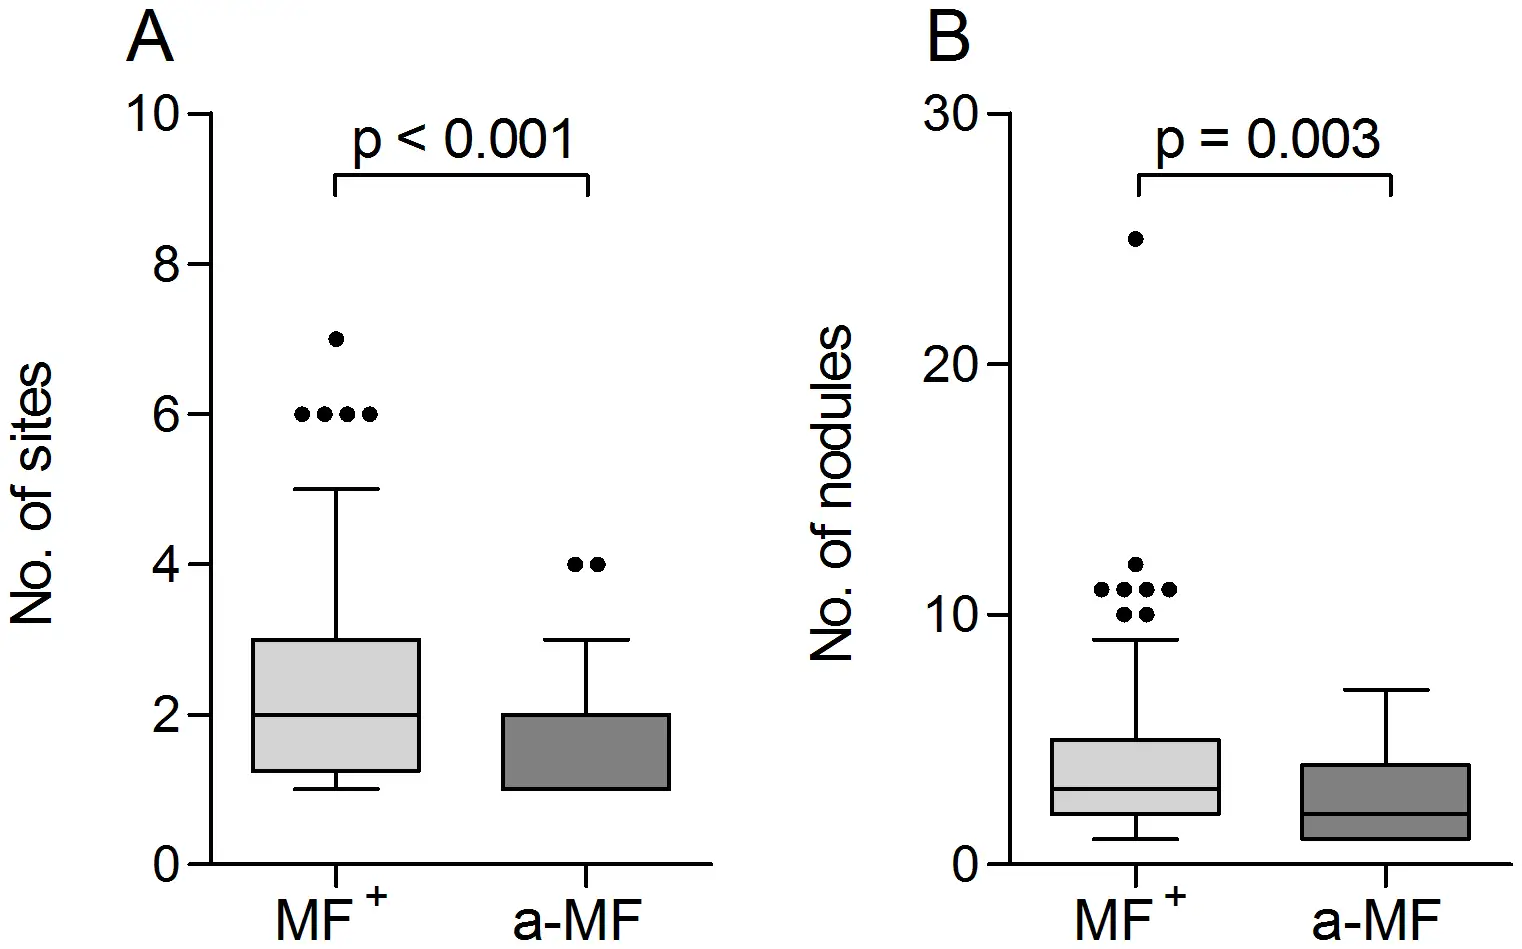

当感染性幼虫进入人体皮肤后,它们会在数月内发育成熟。雄虫相对较小,体长约2至4厘米,细如发丝;而雌虫则可达30至50厘米长,直径约0.3至0.4毫米,是名副其实的"巨虫"。成虫并不四处游荡,它们将自己蜷曲成团,深埋在皮下结缔组织中,形成特征性的纤维结节——医学上称为"盘尾丝虫结节"或"蟠尾蚴瘤"。

这些结节通常出现在骨性突起部位附近,如髋部、肋骨、肩胛骨和头颅。结节大小不一,从豌豆大小到高尔夫球大小不等,触感坚硬,通常无痛。一个感染者体内可能只有一两个结节,也可能多达数十个。在严重感染的病例中,结节几乎可以出现在身体的任何部位,包括头部和眼部周围。

“它就这样完全变白了,“阿科约如此描述他逐渐失去视力的过程。那是一种缓慢的、爬行的失明,始于2010年,在2011年彻底夺走了他的光明。他不得不依赖妻子喂食和穿衣,他的儿子艾托被迫辍学照顾他。艾托的躯干和额头上长着数个"结节”——盘尾丝虫成虫寄生的纤维性肿块。这个家庭被困在一个恶性循环中:疾病夺走了父亲的视力,也夺走了儿子的未来。